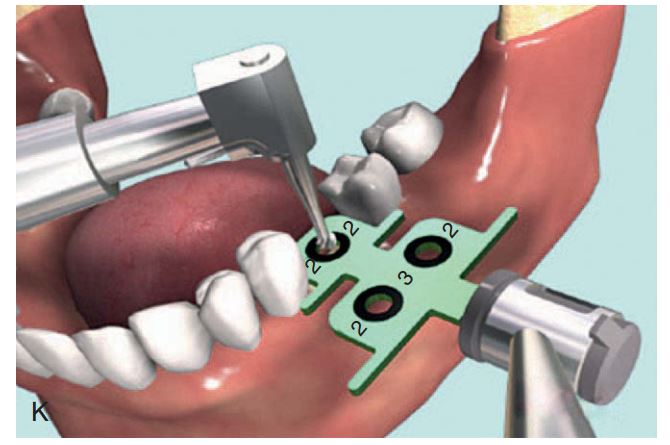

Dụng cụ hướng dẫn định vị Implant

Giúp xác định đúng vị trí đặt Implant và lựa chọn đường kính Implant tối ưu nhất (H2.18). Bộ hướng dẫn ITT gồm có:

– Tấm Titan, giúp hướng dẫn đường kính và vị trí của 1 – 2 Implant.

– Pin đo đạc có phần mở rộng, giúp hướng dẫn đường kính và vị trí Implant ở bệnh nhân không răng.

– Pin song song, để xác định độ song song của Implant.

– Cán của tấm Titan, giúp cầm nắm và đặt tấm Titan vào trong miệng 1 cách an toàn.